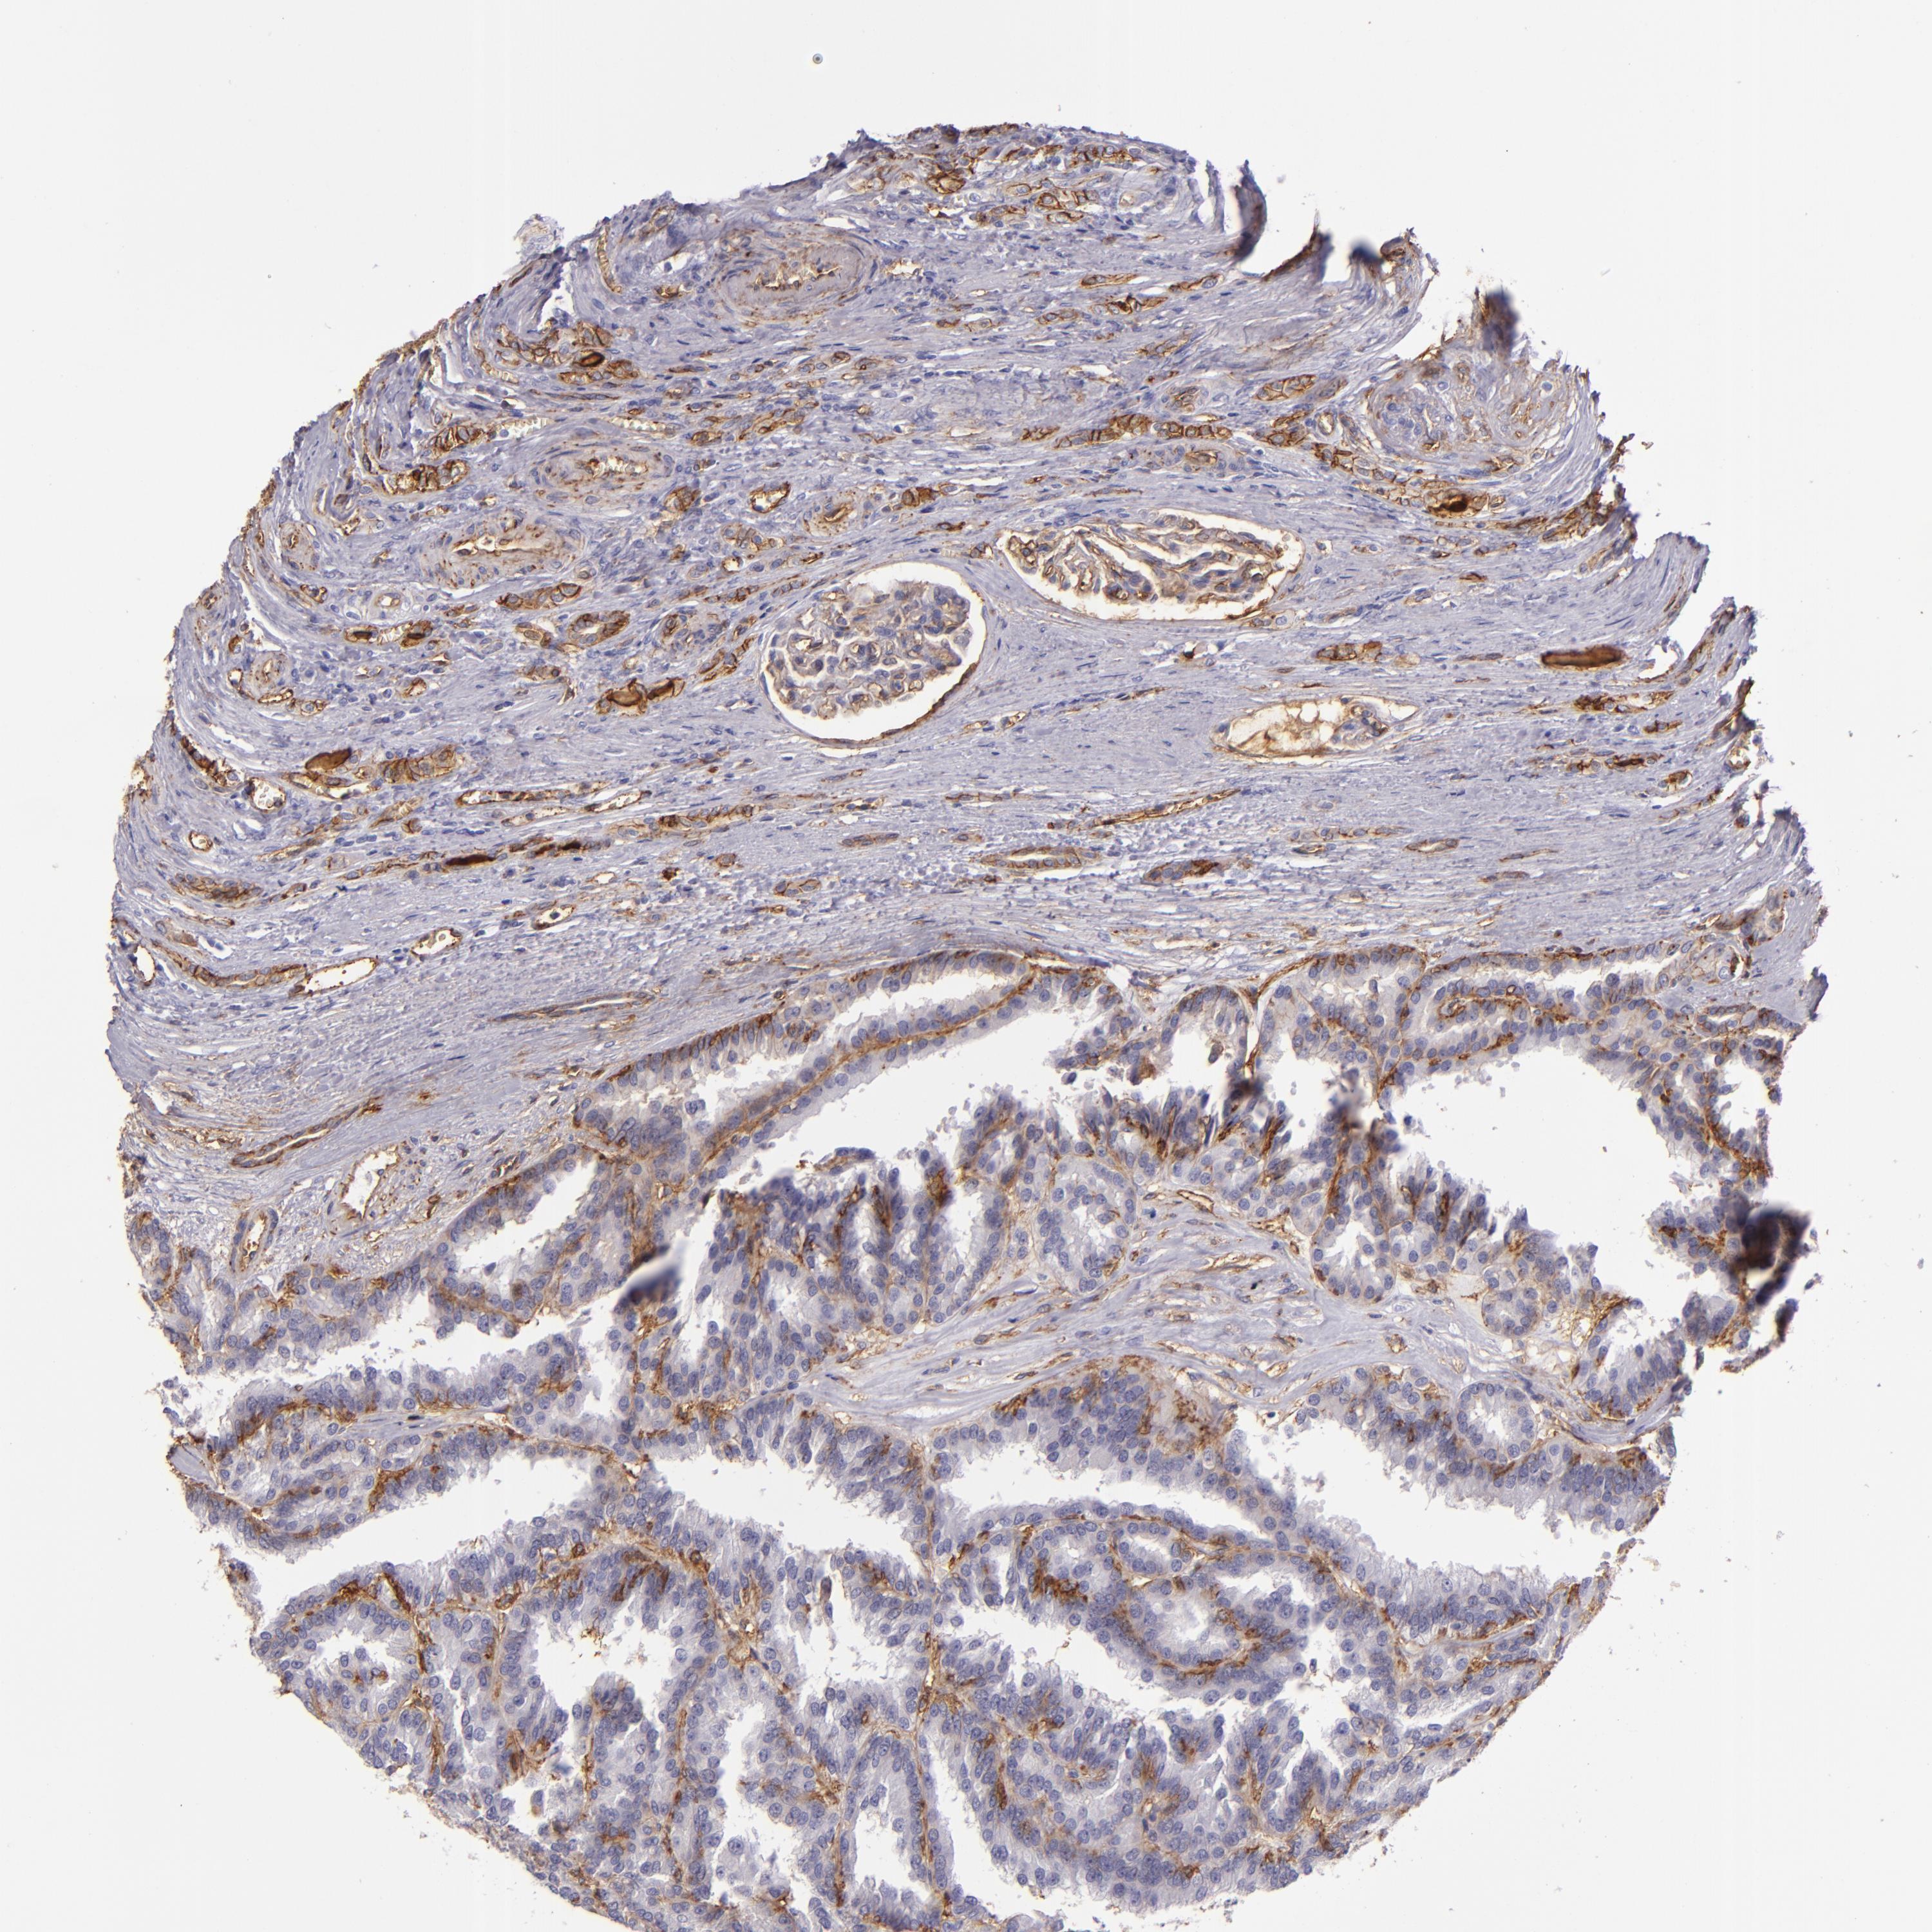

CD9 is validated prognostic, high expression is favorable in Kidney Renal Clear Cell Carcinoma (validation)

KIDNEY RENAL CLEAR CELL CARCINOMA (VALIDATION) - Interactive survival scatter ploti

: 209.22